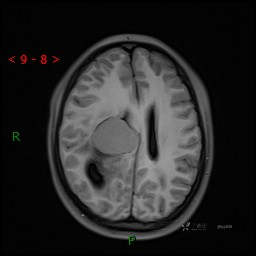

颅脑CT平扫

MRI平扫